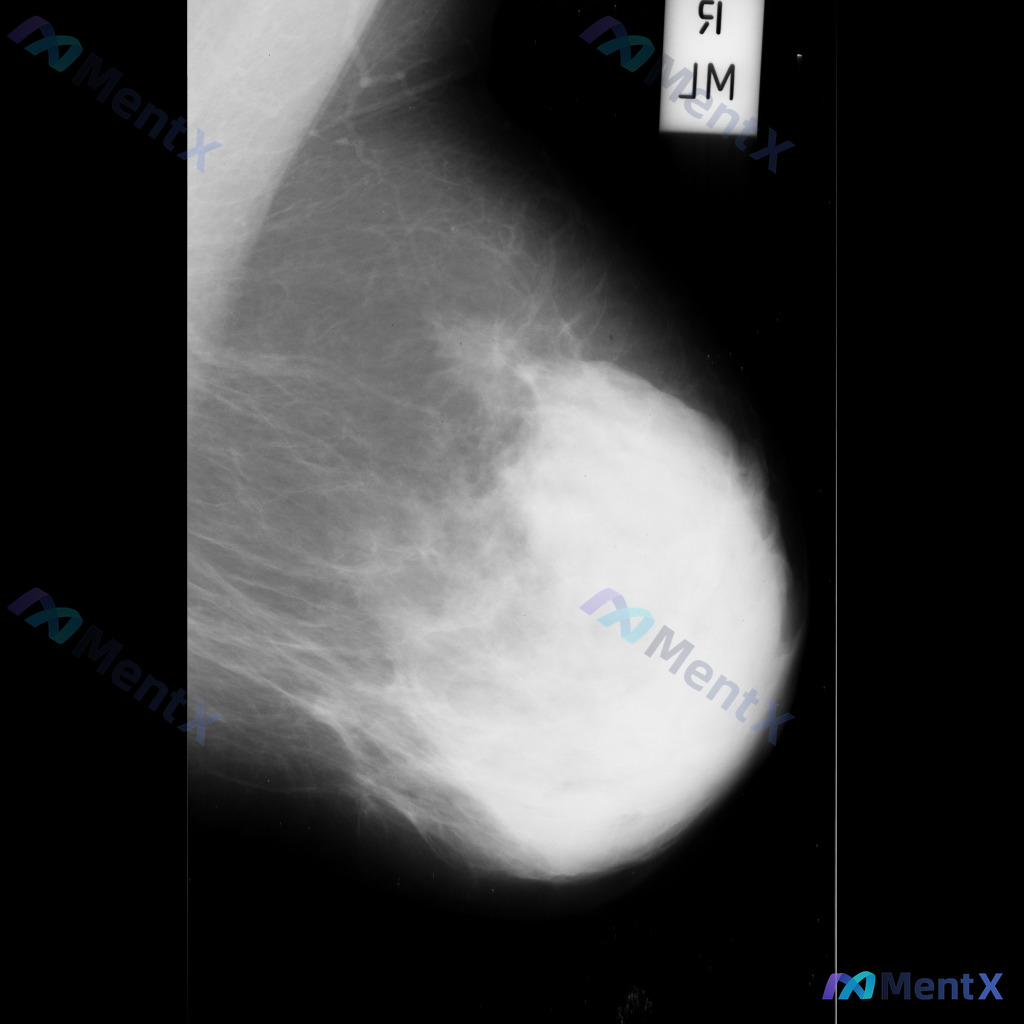

整理到一组乳腺钼靶影像的资料,分享给大家讨论: - 背景:不均匀致密型乳腺(BI-RADS C类) - 主要异常: 1. 乳腺下象限靠近乳头乳晕区,见两个大小不一的圆形/卵圆形高密度影,还有一个较小的类圆形高密度影,密度高于周围腺体,边缘相对清晰但略显模糊; 2. 上述高密度影周围的乳腺下象限,腺体...